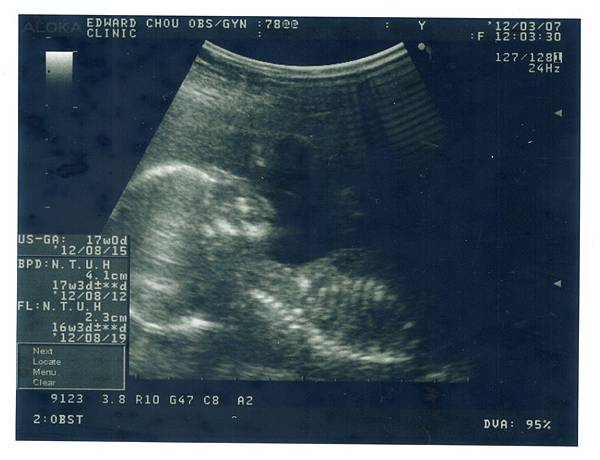

這次產檢結果令馬麻有點沮喪,沮喪到隔一個月才寫上次的產檢心得。余小龍的頭圍比實際週數小四天,腿長比實際週數小十天,馬麻很擔心他會是個大頭小短腿,所以心裡沒有很開心。雖然醫生杯杯說以頭圍為判斷依據,小幾天是沒關係的,但馬麻還是免不了自責,沒有好好養肚肚裡的寶寶。